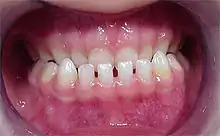

Diastemas em dentes inferiores.